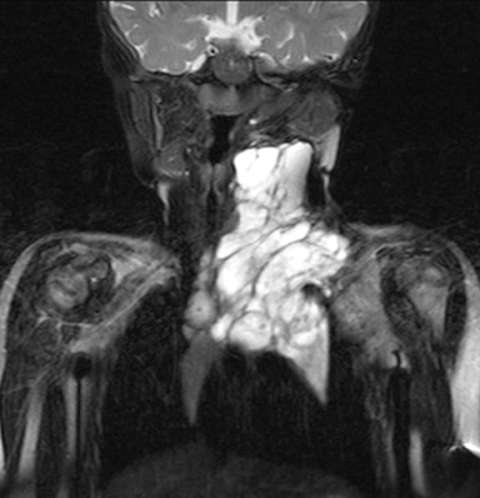

The lesions are most commonly evaluated with contrast enhanced MRI. Occasionally US and CT are used.